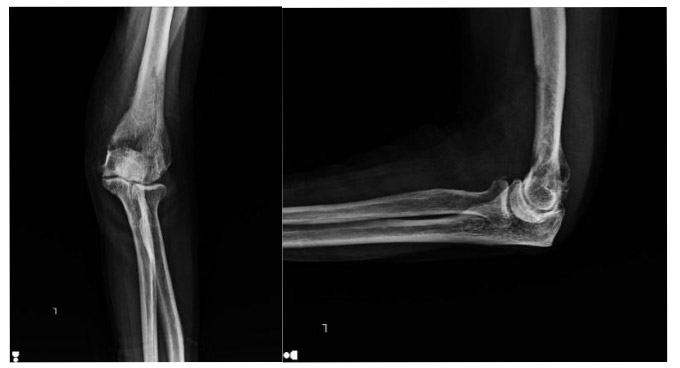

Before the surgery: The X-ray shows an irregularity at the lower end of the humerus.